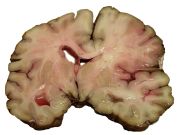

A slice of brain from the autopsy of a person who suffered an acute middle cerebral artery (MCA) stroke

السكتات يمكن تصنيفها في فئتين كبيرتين: قصورية ischemic ونزيفية hemorrhagic.

السكتة القصورية Ischemic stroke

هي سكتة نتيجة قصور في الدورة الدموية الدماغية وتمثل 80% من الحالات. وفيها يقل الدم الواصل لجزء ما في المخ مما يؤدي الى موت هذا الجزي وهذا يكون لسبب من الأسباب الآتية :